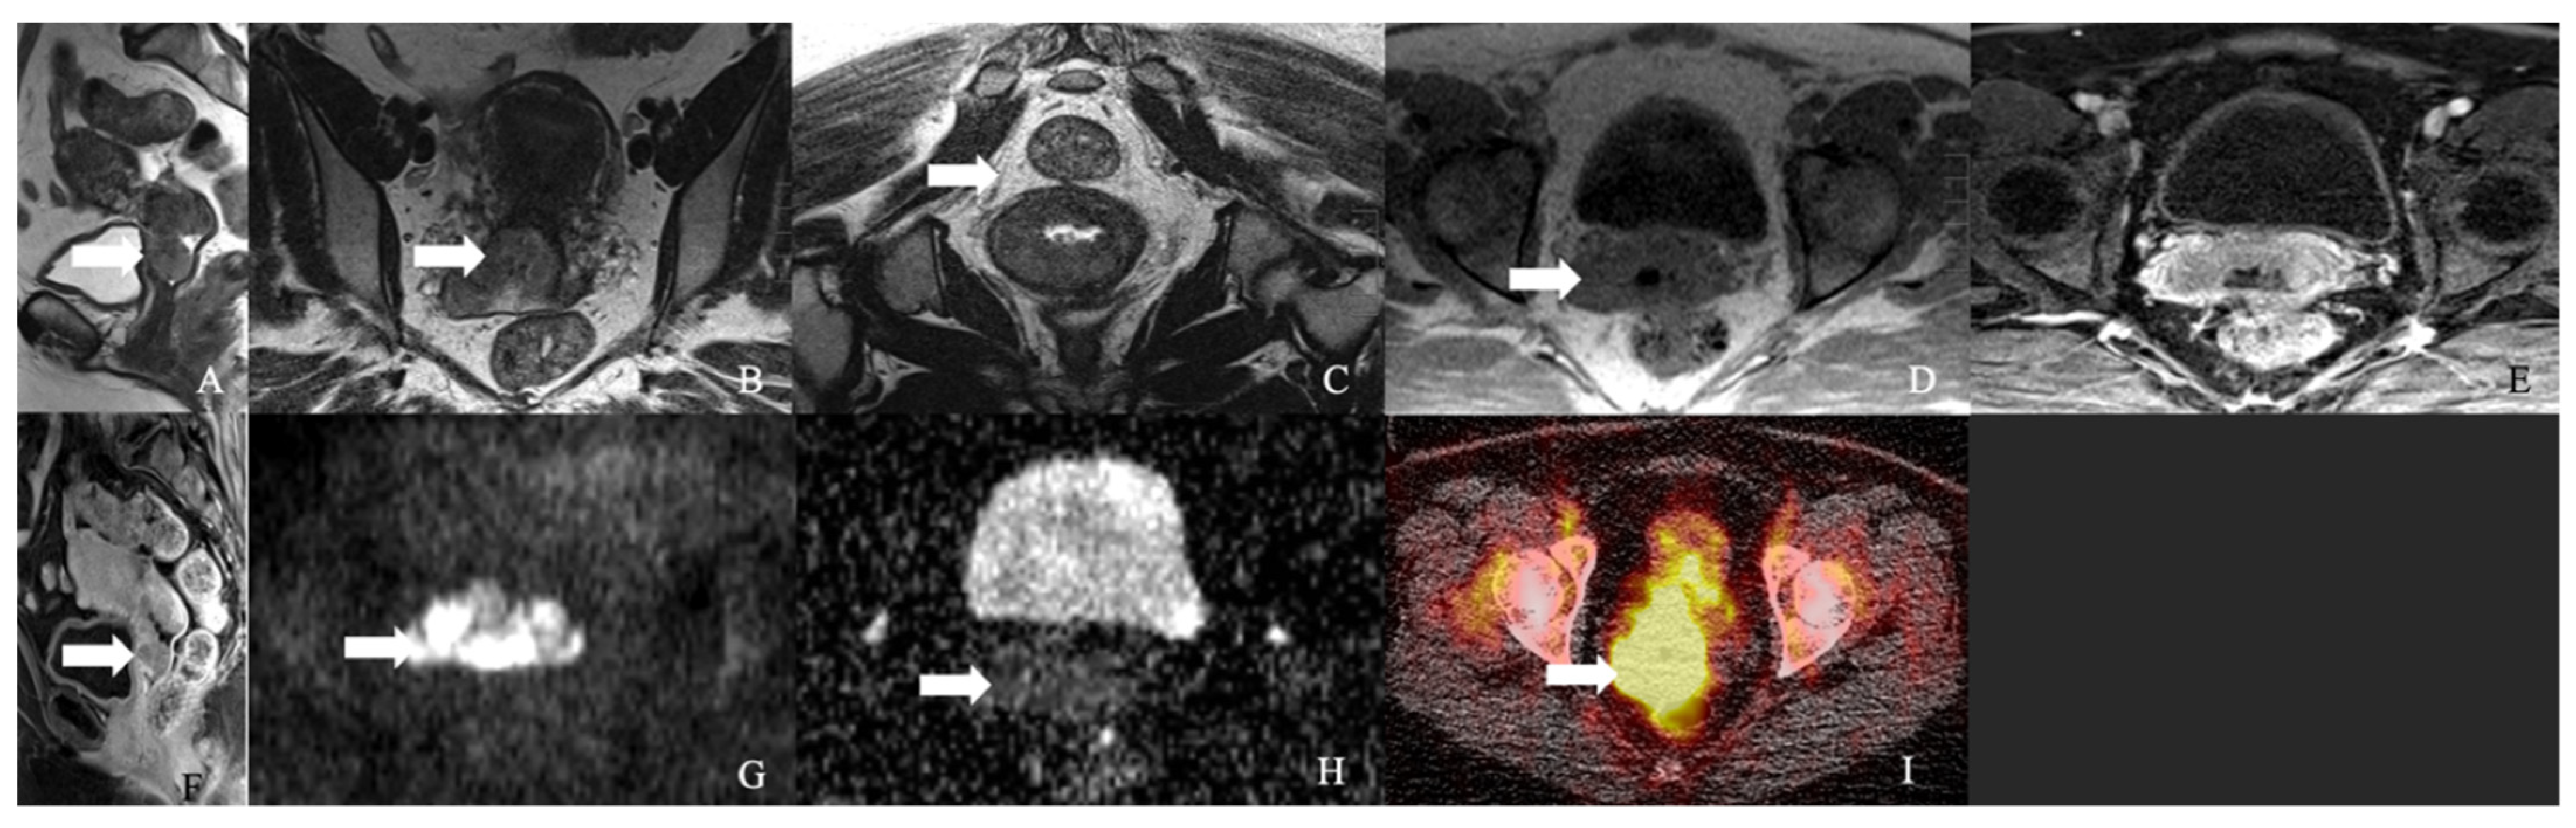

Figure 2. (A,B) Well-differentiated NET grade 1. (A) Well-differentiated neuroendocrine tumor grade 1 (low grade) with an organoid pattern, with a meshwork of thin fibrovascular septa surrounding nests of tumor cells. Tumor cells are uniform with a polygonal shape, round to oval nuclei with salt and pepper chromatin, inconspicuous nucleoli, and moderate to abundant eosinophilic cytoplasm. (B) The Ki67 immunohistochemical stain shows a proliferation rate of 2%. (C,D) Well-differentiated NET grade 2. (C) Neuroendocrine cells in a well-differentiated neuroendocrine tumor, grade 2. Tumor cells are relatively uniform and round. The nuclear chromatin is finely granular. (D) The Ki67 immunohistochemical stain shows a proliferation rate of 10%. (E,F) Well-differentiated NET grade 3. (E) Neuroendocrine cells in a well-differentiated neuroendocrine tumor, grade 3. Tumor cells are relatively uniform and round with eosinophilic cytoplasm. The nuclear chromatin is granular. (F) The Ki67 immunohistochemical stain shows a proliferation rate of 30–40%. (G,H) Poorly differentiated neuroendocrine carcinoma. (G) The tumor shows solid nests of poorly differentiated epithelioid cells with dense chromatin. (H) Ki67 immunohistochemical stain shows a proliferation rate of 80%. (I,J) Small cell carcinoma. (I) Sheets of oval blue cells with minimal cytoplasm. The chromatin is dense. Nuclei demonstrate molding and smudging. (J) Ki67 shows a proliferation index of 80%. (K,L) Large cell neuroendocrine carcinoma. (K) Tumor cells with sheets of large, epithelioid cells. Cytologic features show abundant cytoplasm, coarse chromatin, nuclear pleomorphism, and prominent nucleoli. (L) Ki67 is greater than 90%.